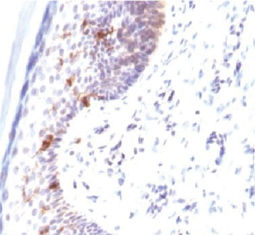

Cell markers are biochemical or genetic characteristics that distinguish and discriminate between different cell types. Although most are molecules expressed on the plasma membrane, cell markers are not limited to surface antigens and can include other components such as transcription factors. The unique composition and combination of cell markers allows researchers to accurately delineate the various cell types within a population. As the fields of regenerative medicine and molecular diagnostics continue to expand, the need to discover and describe novel cell-specific markers will become even more urgent.

GeneTex is proud to offer an outstanding selection of antibody reagents to facilitate your research, featuring antibodies against unique cell markers for detection of the various cell types highlighted below.